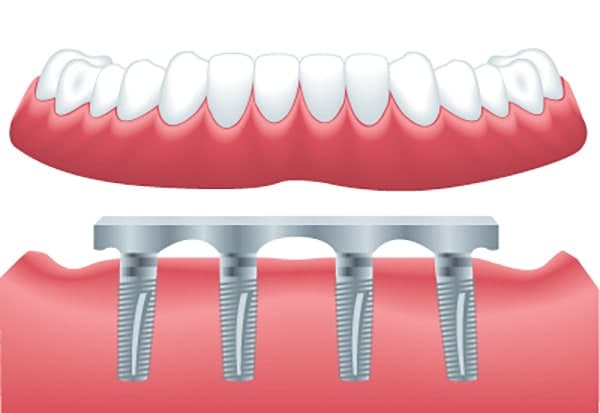

اوردنچر (Overdenture) نوعی پروتز دندانی است که به منظور جایگزینی دندان های از دست رفته در فک بالا یا پایین استفاده می شود. برخلاف پروتزهای دندانی سنتی که به طور کامل روی لثه قرار می گیرند، اوردنچرها به ایمپلنت های دندانی متصل می شوند و به همین دلیل از استحکام و پایداری بیشتری برخوردار هستند.

ایمپلنت ها به عنوان پایه ای برای اوردنچر عمل می کنند و پروتز را به طور محکم در جای خود نگه میدارند. این نوع پروتزها به دلیل اتصال به ایمپلنت، احساس راحتی بیشتری برای بیمار به همراه دارند و احتمال لغزش یا جابجایی آنها حین صحبت کردن یا غذا خوردن بسیار کمتر است.

در اوردنچر متحرک، پروتز به ایمپلنت ها متصل شده اما قابلیت جدا شدن از آنها را دارد. این نوع اوردنچر با استفاده از اتصالات خاص مانند کلیپ ها یا گیره ها روی ایمپلنت ها ثابت می شود و بیمار می تواند به راحتی آن را برای تمیز کردن یا هنگام خواب خارج کند. اوردنچر متحرک برای افرادی که نیاز به نگهداری ساده و انعطاف پذیری در استفاده دارند، گزینه مناسبی است. در این روش، حداقل دو یا چهار ایمپلنت در فک کاشته می شود تا پایداری و استحکام لازم را برای پروتز فراهم کند.

در مقابل، اوردنچر ثابت به ایمپلنت ها به طور دائم متصل می شود و بیمار نمی تواند آن را به راحتی خارج کند. این نوع اوردنچر از نظر عملکرد و احساس، به دندان های طبیعی نزدیک تر است و به بیمار اجازه می دهد با اطمینان بیشتری غذا بخورد و صحبت کند.

اوردنچر ثابت معمولا به ایمپلنت های بیشتری نسبت به نوع متحرک نیاز دارد و اغلب به شش تا هشت ایمپلنت در هر فک برای نگه داشتن پروتز نیاز است. این روش بیشتر برای افرادی توصیه می شود که به دنبال یک راه حل دائمی و پایدارتر هستند و تمایل به کاهش نگهداری روزانه دارند.